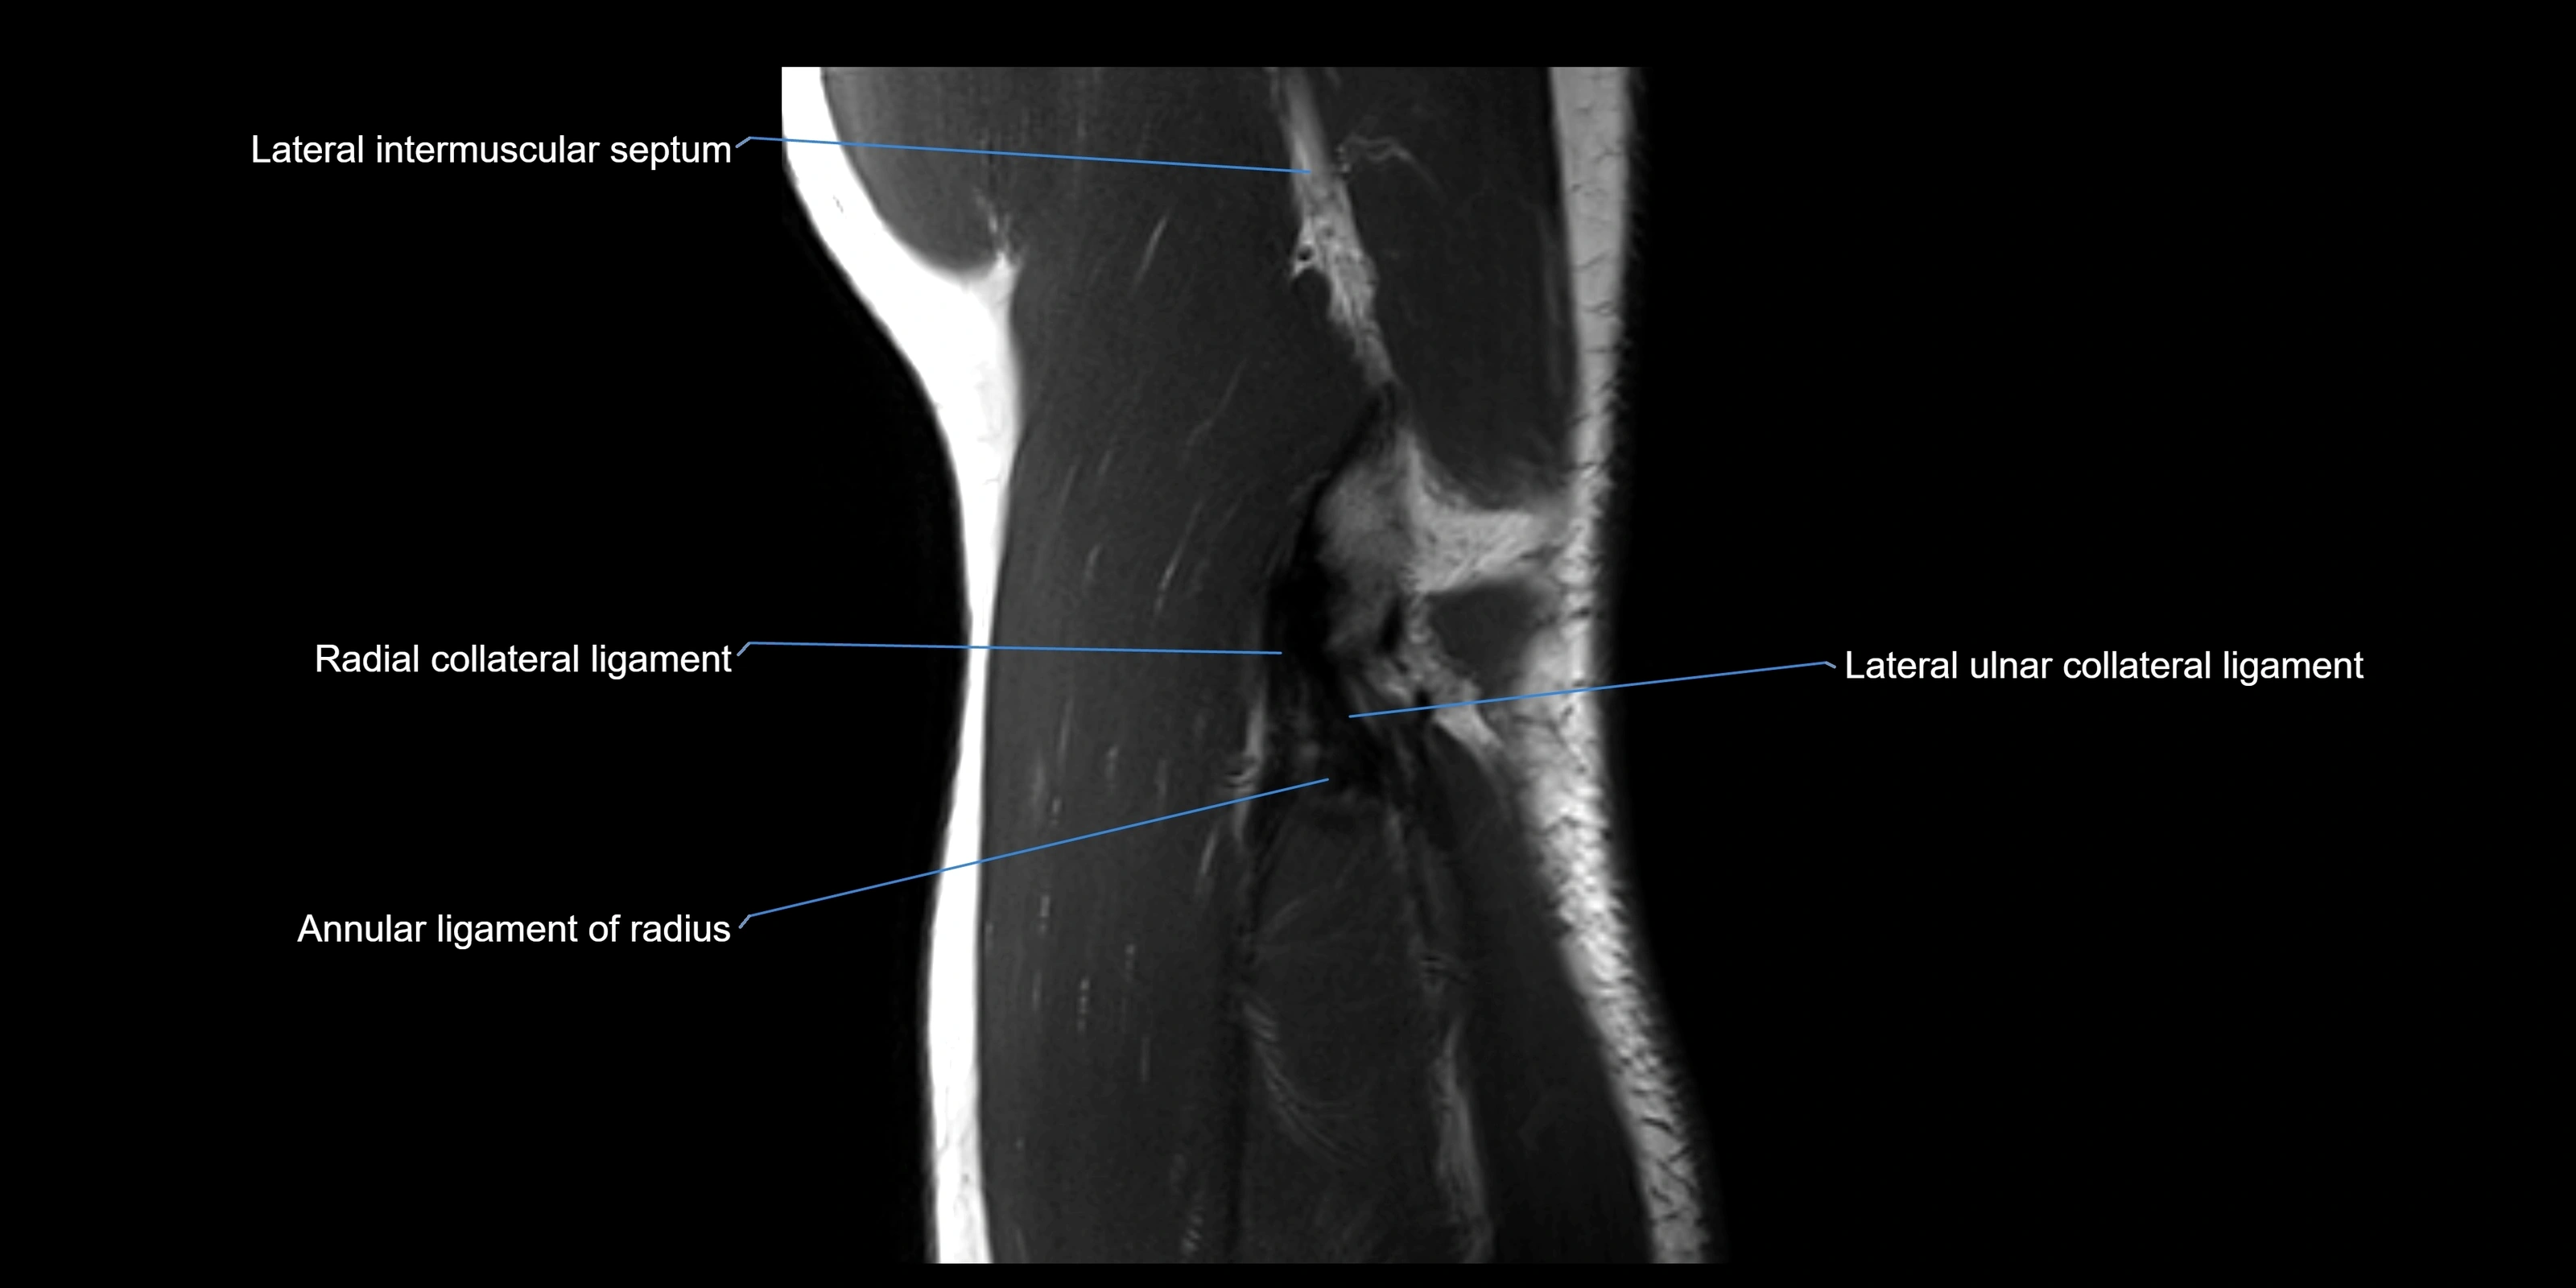

MRI Appearance

T1-weighted images:

• Ligament: low signal intensity (dark), appearing as a continuous band around the radial head.

• Adjacent fat and marrow: bright, creating contrast with the ligament.

• Thickening or disruption indicates injury or fibrosis.

• Joint capsule and synovium seen as thin low-signal lines contiguous with ligament margins.

T2-weighted images:

• Ligament: low signal (dark) with clear delineation from joint fluid.

• Fluid or edema: bright hyperintense, separating or surrounding the ligament in partial tears.

• Complete tear: discontinuity or non-visualization of ligament fibers, often with joint effusion.

MRI images

image